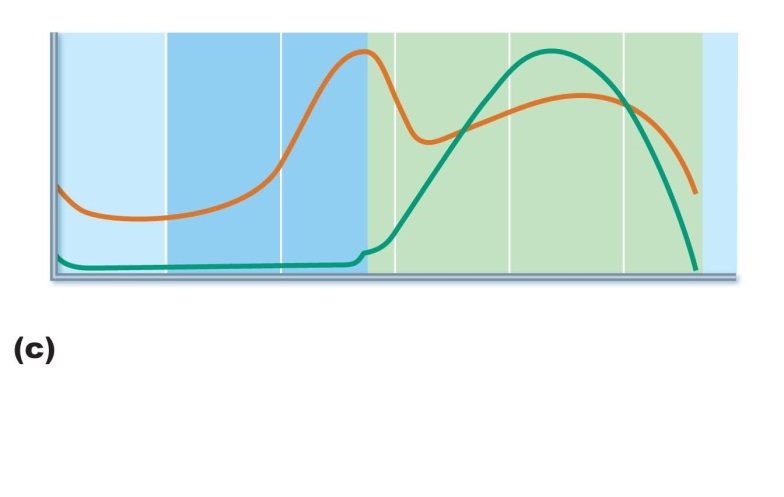

progesterone level in a normal uterine cycle

names of hormones during pregnancy

first long graph is beta hCG

second one is estrogen

third is progesterone